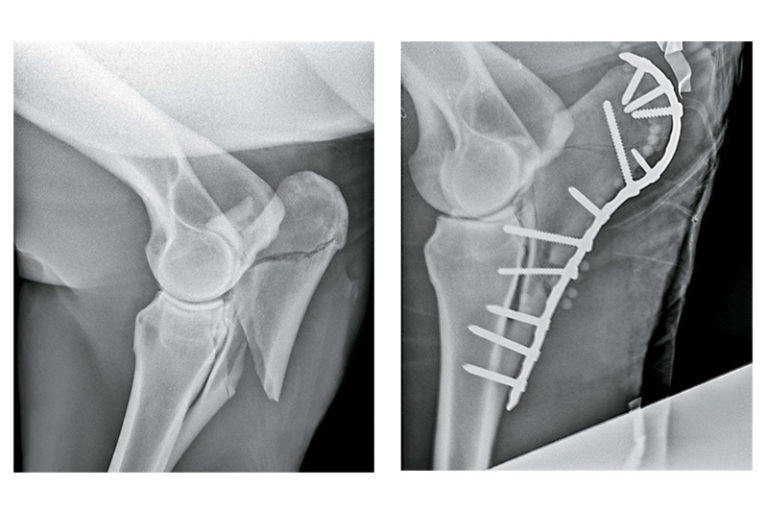

Comparison of 3D‐assisted surgery and conservative methods for treatment of type III fractures

Fractures of the Elbow in Horses Musculoskeletal System Merck Veterinary Manual Horse Face Fracture Fracture of these bones can result in trauma to the eye, sinuses, zygomatic process, nasal passages, nasolacrimal duct and cranial nerves. Usually, they’re wounds or cuts on the legs—but sometimes, they’re on the horse’s. The aim of surgical repair is. Injuries to the equine head are common, particularly in young horses, possibly due to their inquisitive and excitable nature. By. Horse Face Fracture.